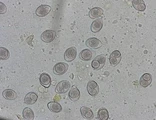

Picture Hint Answer % Correct

Cestode Anoplocephala

100%

Protozoaire Cryptosporidium

Cestode Dipylidium caninum

Protozoaire Giardia

Protozoaire Isospora ou Eimeria

Cestode Moniezia

Protozoaire Sarcocystis

Cestode Taenia

Protozoaire Toxoplasma